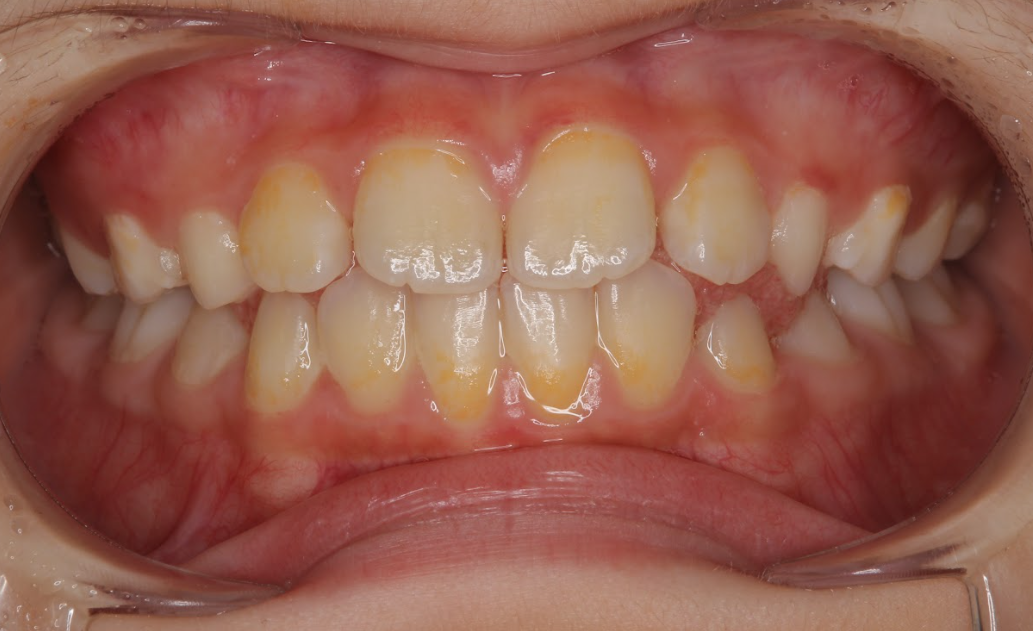

小児矯正(Ⅰ期治療)により交叉咬合および歯列不正を改善した症例(8歳女児)

治療後 ![]() |

成長期の顎の発育を利用した小児矯正(Ⅰ期治療)を行い、歯列の拡大と咬合の改善を図りました。混合歯列期(6EDC2112CDE6)において永久歯が正しく並ぶためのスペース確保を目的に治療を進めました。定期的な調整と経過観察を行いながら咬合誘導を行いました。 |

| 術後の経過・現在の様子 |

歯列の幅が拡大され、交叉咬合は改善しました。前歯の配列も整い、咬合バランスが安定しています。永久歯が並ぶためのスペースも確保され、将来的な歯列不正のリスクが軽減された状態です。必要に応じて永久歯列完成後にⅡ期治療を検討します。 |